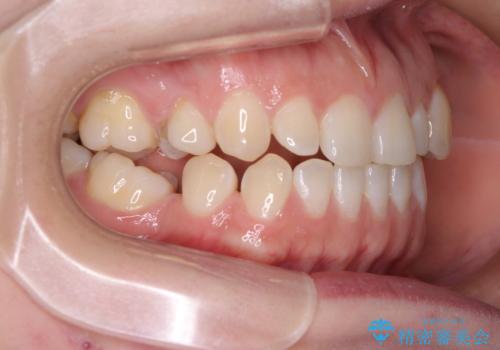

傾斜した下顎の奥歯は、矯正治療にてまずは歯軸を改善させ、隙間が閉じられるようであればそのままに、閉じられないようであればインプラント治療を行うこととしました。

上顎のむし歯の酷い残存乳歯は抜歯をし、矯正治療の途中でインプラントを埋入、矯正治療後に補綴治療を行うこととしました。